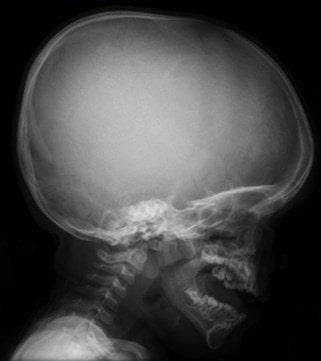

Este tipo de enanismo se caracteriza por la disminución del crecimiento del tejido óseo (menos de 130 cm de altura). La mayoría de los pacientes presentan deformación de la columna vertebral, macrocefalia, nariz en silla de montar y longitud anómala de las extremidades.

La acondroplasia se presenta con más frecuencia en mujeres. Al nacer, los niños con esta patología tienen un crecimiento reducido y la circunferencia de la cabeza es inusualmente grande. Algunas características típicas que presentan los pacientes con acondroplasia son:

Cabeza grande con frente convexa

Uno de los principales síntomas neurológicos es el desarrollo insuficiente de la base del cráneo y el canal espinal, lo que puede causar compresión en la médula y el bulbo raquídeo. La circulación del líquido cefalorraquídeo pude verse afectado.

El diagnóstico se puede hacer al nacer sobre la base de ciertas características típicas de la acondroplasia o desde el útero a través de una prueba de selección genética. En algunos niños, estas características físicas son menos obvias al nacer, y aproximadamente el 20% de los niños son diagnosticados más tarde, durante el primer año de vida.

Las evaluaciones físicas se hacen en base a la apariencia del paciente, donde los rasgos faciales y corporales son determinantes. El especialista evaluará la circunferencia craneal, longitud de extremidades y proporción corporal a través de tablas de medidores de crecimiento.

Una prueba de ADN puede demostrar la mutación en el gen FGFR 3. Las pruebas de rayos X más usada son las de cráneo, tórax, columna vertebral, pelvis huesos y articulaciones. Que pueden demostrar desproporción entre el cerebro y el cráneo, deformación en el esternón y costillas, cifosis, cambio de los huesos ilíacos, deformidad en las articulaciones, entre otros.